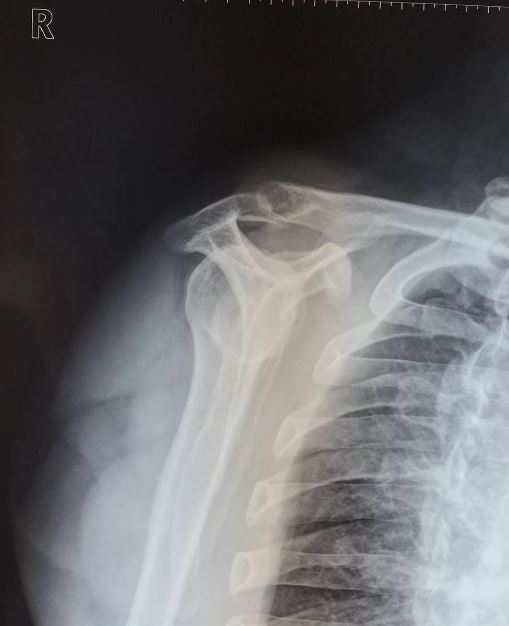

三型:钩状肩峰(40%).

使得肩袖所在这条"缝隙"变小:肩峰形态分3类,1型平坦,2型弧形,3型钩状

先天因素:肩峰形状呈钩状.

美国肩关节专家bigliani将肩峰形态分型分成哪三种类 - 好大夫在线